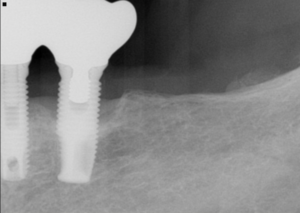

まず骨の状態です。授乳期は、赤ちゃんに必要な栄養を支えるため、体の代謝が普段と変わります。すべての方の骨が弱くなるわけではありませんが、食事量の低下、体重減少、日光に当たる時間の不足、慢性的な寝不足が重なると、骨の回復力に影響することがあります。インプラントは骨の中で固定を得る治療なので、骨の幅、高さ、硬さを断層撮影で確認することが欠かせません。断層撮影とは、骨の厚みや神経の位置を立体的に把握する検査です。

米国の補綴教育では、治療法そのものより、診断の順序を厳密に考えます。どこに入れるかの前に、なぜ失ったか、再発要因は何か、治療後にどこへ力が逃げるかを整理します。日本の保険診療では短時間で結論を求められる場面もありますが、自由診療で質を守るには、むしろここに時間を使うべきだと感じています。名古屋 インプラント 授乳中の相談でも、実際に診てみると、問題の中心が欠損部ではなく、歯周病や食いしばりであることは珍しくありません。

再治療症例から学ぶことも多くあります。以前に他院で入れたインプラントが緩んだ方の中には、骨そのものより、上の被せ物の形態や噛み合わせの設定に無理があったケースが見られます。とくに臼歯では、噛む力が体重の二倍から三倍近くに達することがあります。そのため上部構造の接触は、天然歯と全く同じ強さにするのではなく、力の逃がし方まで考えて設計します。長持ちさせる考え方は、

・断層撮影で骨条件が整っているか